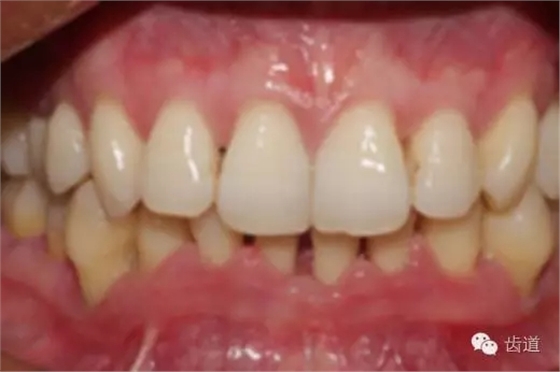

2、牙齦

(顏色、形狀、質(zhì)地、退縮、BOP、PD、附著齦)